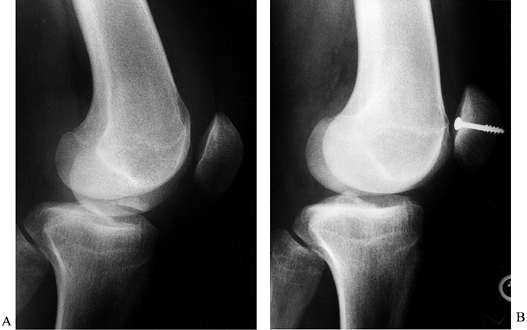

Two screws give best control of rotation and provide secure internal fixation of the OCD fragment (Fig. 84.33).

Figure 84.33. Open reduction internal fixation (ORIF) of osteochondritis lesion of medial femoral condyle. -

Use cannulated screws, noncannulated 4.0 cancellous bone screws, or Herbert screws for fixation (33).

In skeletally immature patients, it is important not to cross the epiphyseal line with the threaded screw.

Use an image intensifier to determine screw placement accurately.

Countersink the head of the screw just below the articular cartilage surface.